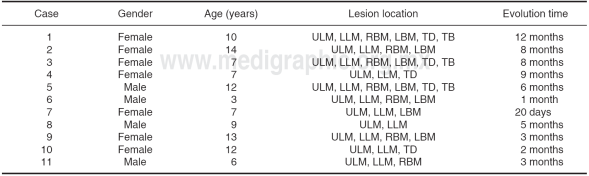

Out of a total of 11 patients, 63.64% were female. Average age was 9.0 ± (SD:3.41). Most affected sites in the mouth were upper and lower labial mucosa in 100% cases, right and left oral mucosa in 63.64% cases, dorsal side of the tongue in 45.45% cases and lateral border of the tongue in 27.27% cases (Table I). Anatomical and pathological study revealed presence of epithelial acanthosis, papillomatosis and koilocytosis in 100% of cases.

Table I Case distribution according to gender, age, lesion location and evolution time.

ULM = Upper labial mucosa, LLM = Lower labial mucosa, RBM = Right buccal mucosa, LBM = Left buccal mucosa, TD = Tongue dorsum, TB = Tongue border.

The greatest number of acid application was three and four times per case, representing 27%, with average of 4.0 ± (SD:2.0), lesion disappearance average was 61.3 days ± (SD:28.8) and relapse was not present in 100% of all cases (Table II).